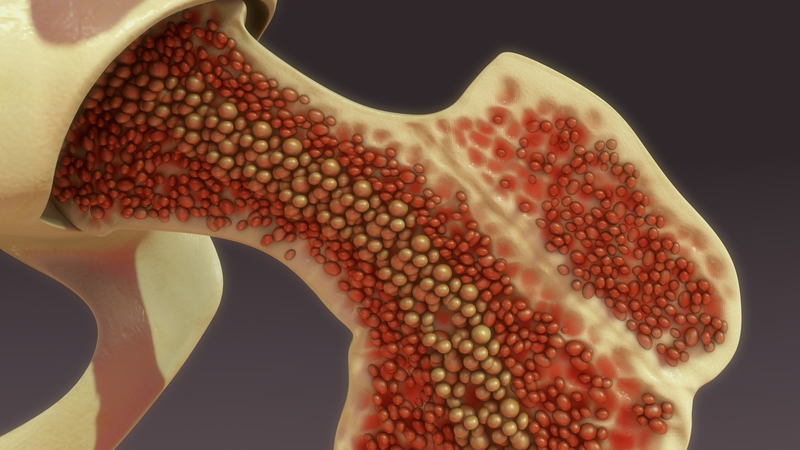

Obsah: Čo je kostná dreň? Čo robí kostná dreň? Anatómia kostnej drene Aké sú bežné stavy a por...

Obsah: Čo je zlyhanie kostnej drene? Typy zlyhania kostnej drene Ako časté je zlyhanie kostnej ...